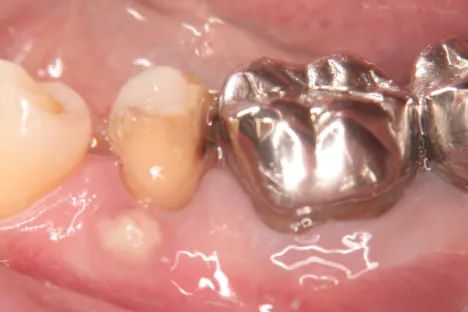

Dr.-Taniguchi_Fig.6

Fig. 6. During secondary surgery: A sufficient amount of bone regenerated around the fixture, and favorable secondary fixation was obtained.